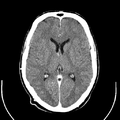

Computed tomography of human brain, from base of the skull to top. Taken with intravenous contrast medium.